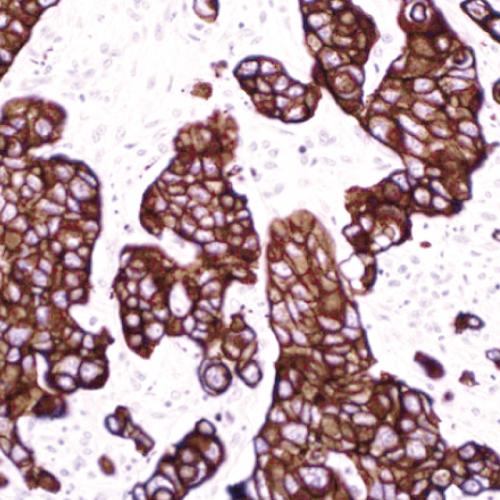

B細(xì)胞合成的免疫球蛋白是一個多聚體,它由2個重鏈和2個輕鏈(Lambda)組成。在不同階段或同一階段產(chǎn)生幾種不同類型的重鏈,但輕鏈都為同一型,即Kappa鏈。正常淋巴結(jié)中表達(dá)不同輕鏈的B細(xì)胞數(shù)κ∶λ約為2∶1。Lambda的表達(dá)受限提示單克隆增生和腫瘤形成。腫瘤性增生時呈限制性表達(dá),即只有一條輕鏈κ或λ表達(dá),相反如果檢測結(jié)果為κ和λ都看到表達(dá),則沒有限制性,為增生性病變。在B細(xì)胞淋巴瘤中,免疫球蛋白輕鏈κ和λ往往呈特異性限制性表達(dá),是B細(xì)胞單克隆性增生的標(biāo)志。因此在臨床上,測定 κ/λ 比值可用于區(qū)分腫瘤B細(xì)胞增殖和反應(yīng)性淋巴樣增生。

由于組織中富含免疫球蛋白,因此采用免疫組化技術(shù)檢測Lambda會伴隨大量背景染色的形成,這將影響染色結(jié)果判讀。而原位雜交探針具有高度特異性,在石蠟切片中容易涉透到組織中去與靶標(biāo)雜交,并且得到穩(wěn)定優(yōu)質(zhì)的染色結(jié)果。

Lambda鏈探針試劑,分別針對Lambda鏈mRNA序列特異設(shè)計靶點檢測,具有高度特異性和敏感性。通過多聚體酶標(biāo)技術(shù)-DAB顯色系統(tǒng),極大提高了檢測信號強(qiáng)度。

1、胞漿染色定位清晰,陽性信號對比度高。不存在交叉反應(yīng),避免了免疫組化檢測的高背景,染色結(jié)果可直接進(jìn)行判讀。